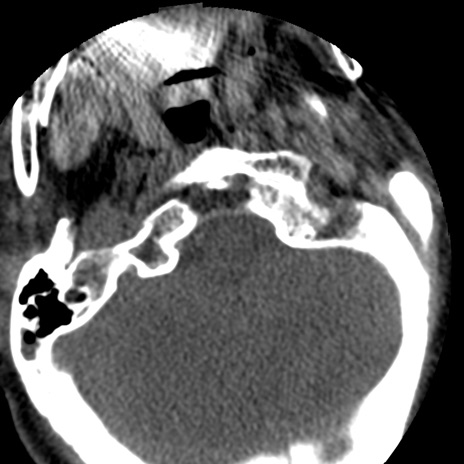

症例50 頚椎CT(横断像)

矢状断像